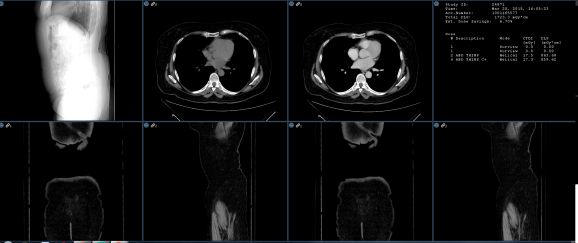

Selected Study

When this option is selected along with the Grids matrix layout, a selected study in the thumbnail panel can be designated for image frame loading. When the user clicks on the thumbnail study header a yellow border will surround the images. Those will load into the frames in the same order of the thumbnail study as shown below.

When loading priors, selecting the study header and highlighting the series will only load those selected priors after grid matrix frame layout is created.